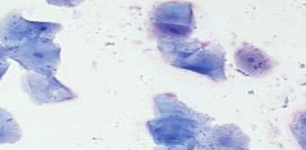

What stain do you use for vaginal cytology*

Schorr’s stain

Which phase of estrus? Why?

Proestrus